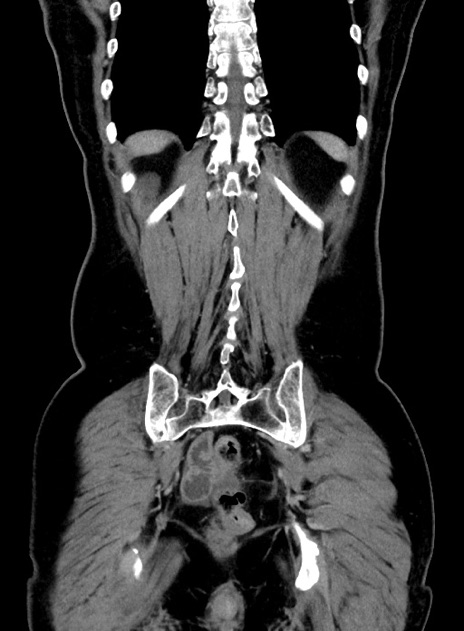

症例9(冠状断像)

【症例】 60歳代女性

【主訴】むかつき、みぞおちの痛み

【現病歴】3日前よりむかつきがあり、食事がとれない。

【既往歴】糖尿病

【身体所見】発熱なし、心窩部圧痛軽度あるも、腹膜刺激症状なし。

【データ】WBC 7400、CRP 1.92